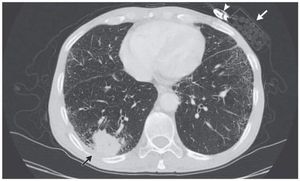

A person who sent a CT scan to the insurance company for which he is insured for his life .. Which shows the presence of lung cancer "marked by a black arrow" .. Because they pay him the expenses of treatment - The insurance company sent him the same picture and pointed to him on a pack of cigarettes and soldering white arrow ..